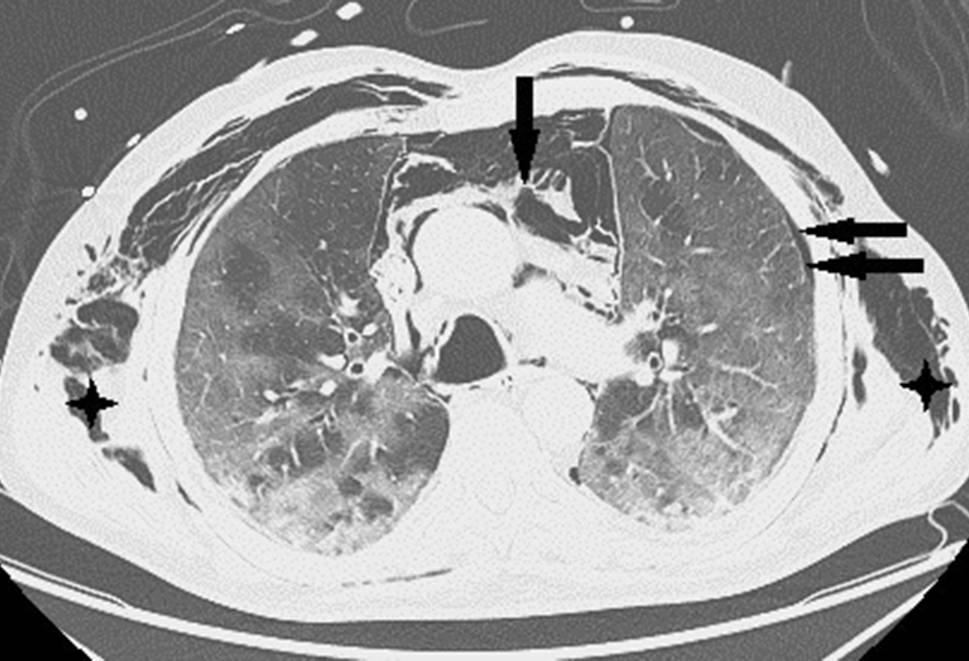

Ein 71-jähriger Patient wurde aufgrund rasch zunehmender respiratorischer Insuffizienz aufgenommen. Das Thorax-CT bei der Aufnahme zeigte bilaterale milchglasartige Verschattungen mit Punctum maximum in den Unterlappen (Abb. 1). Die PCR bestätigte die Infektion mit SARS-CoV‑2. Seit 9 Tagen bestanden Myalgien, Diarrhö und Anosmie. Anamnestisch lag Asthma bronchiale unter Bedarfstherapie vor. Die Kreislaufparameter waren unauffällig, die Temperatur subfebril. Unter Raumluft war die Sauerstoffsättigung 78 %, unter 9 l O2/min Maskenatmung 92 %. Die Atemfrequenz war auf 52/min gesteigert. Im Labor waren CRP auf 104 mg/l (Normwert 0–5), Ferritin auf 2295 ng/ml (NW 18–360) und IL 6 auf 133 pg/ml (NW 0–7) erhöht. Nach Einleitung antibiotischer, antimykotischer und antiviraler Therapie mit Ampicillin/Sulbactam, Azithromycin und Posaconazol, sowie Dexamethason, Remdesivir und Aciclovir wurde der Patient an der Intensivstation aufgenommen.

Abb. 1

SARS-CoV‑2-Pneumonie: Milchglasverschattungen (Pfeile)

Nach 24 h nichtinvasiver Beatmungsversuche war wegen rasch progredienter, respiratorischer Verschlechterung die Intubation erforderlich. Durch Bauchlagerung und Optimierung der Beatmungsparameter gelang eine vorübergehende Stabilisation der Oxygenierung mit Oxygenationsindizes (OI) bis 150. Am Tag 13 fiel ein rasch progredientes Weichteilemphysem an Hals und linkem Hemithorax auf. Das Thorax-CT zeigte multiple Milchglastrübungen („ground-glass opacity“), Parenchymkonsolidierungen sowie einen schmalen Pneumothorax links mit einer apikalen Spaltbreite bis maximal 15 mm. Zusätzlich bestanden ein ausgedehntes Pneumomediastinum und bilaterales Weichteilemphysem am Thorax (Abb. 2). Nach Anlage einer linksseitigen Thoraxdrainage war das Weichteilemphysem zunächst rückläufig. Wegen dessen erneuter, rascher Zunahme wurden rechts und links je eine weitere Thoraxdrainage gelegt, obwohl rechts kein Pneumothorax nachweisbar war. Danach war das Weichteilemphysem kontinuierlich regredient, die Lungen blieben expandiert. Trotzdem verschlechterte sich die respiratorische Situation unaufhaltsam. Der Patient verstarb nach 17 Tagen invasiver Beatmung (Pressure-Support-Ventilation-Modus, Spitzendrücke 28 mbar, durchschnittlicher „driving pressure“ 17 mbar) und begleitender, intensivmedizinischer Maßnahmen infolge kardiorespiratorischen Versagens.

Abb. 2

Ausgedehntes Pneumomediastinum (Pfeil) bei nur minimal ausgeprägtem Pneumothorax (2 Pfeile). Weichteilemphysem am gesamten Thorax (Sterne)